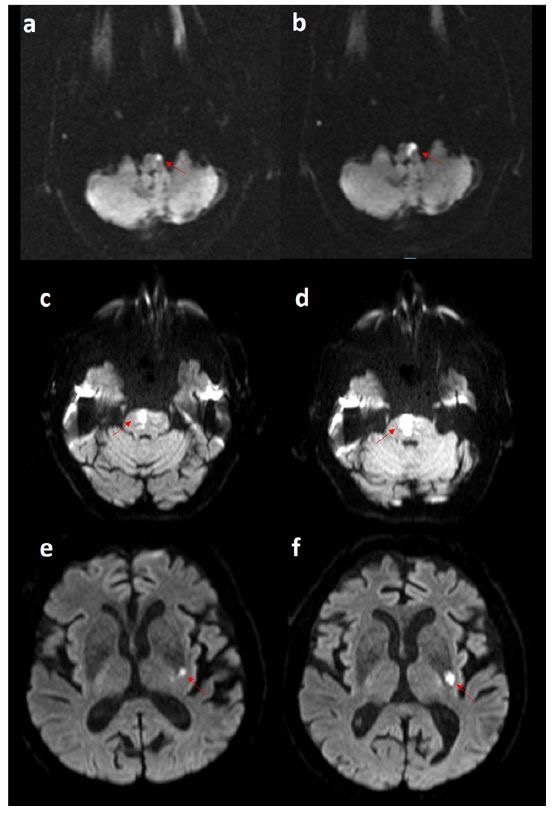

“Treatment of Early Neurological Deterioration in Lacunar Stroke” (in Medicina Clínica).

Early neurological deterioration (END) in lacunar stroke is a relevant clinical phenomenon during the first days of hospitalization and still lacks a standardized therapeutic approach.

In this retrospective cohort (2013–2023), we describe the clinical presentation, independent predictors, and the therapeutic strategies implemented in real-world practice, and we assess their association with 90-day functional outcomes.